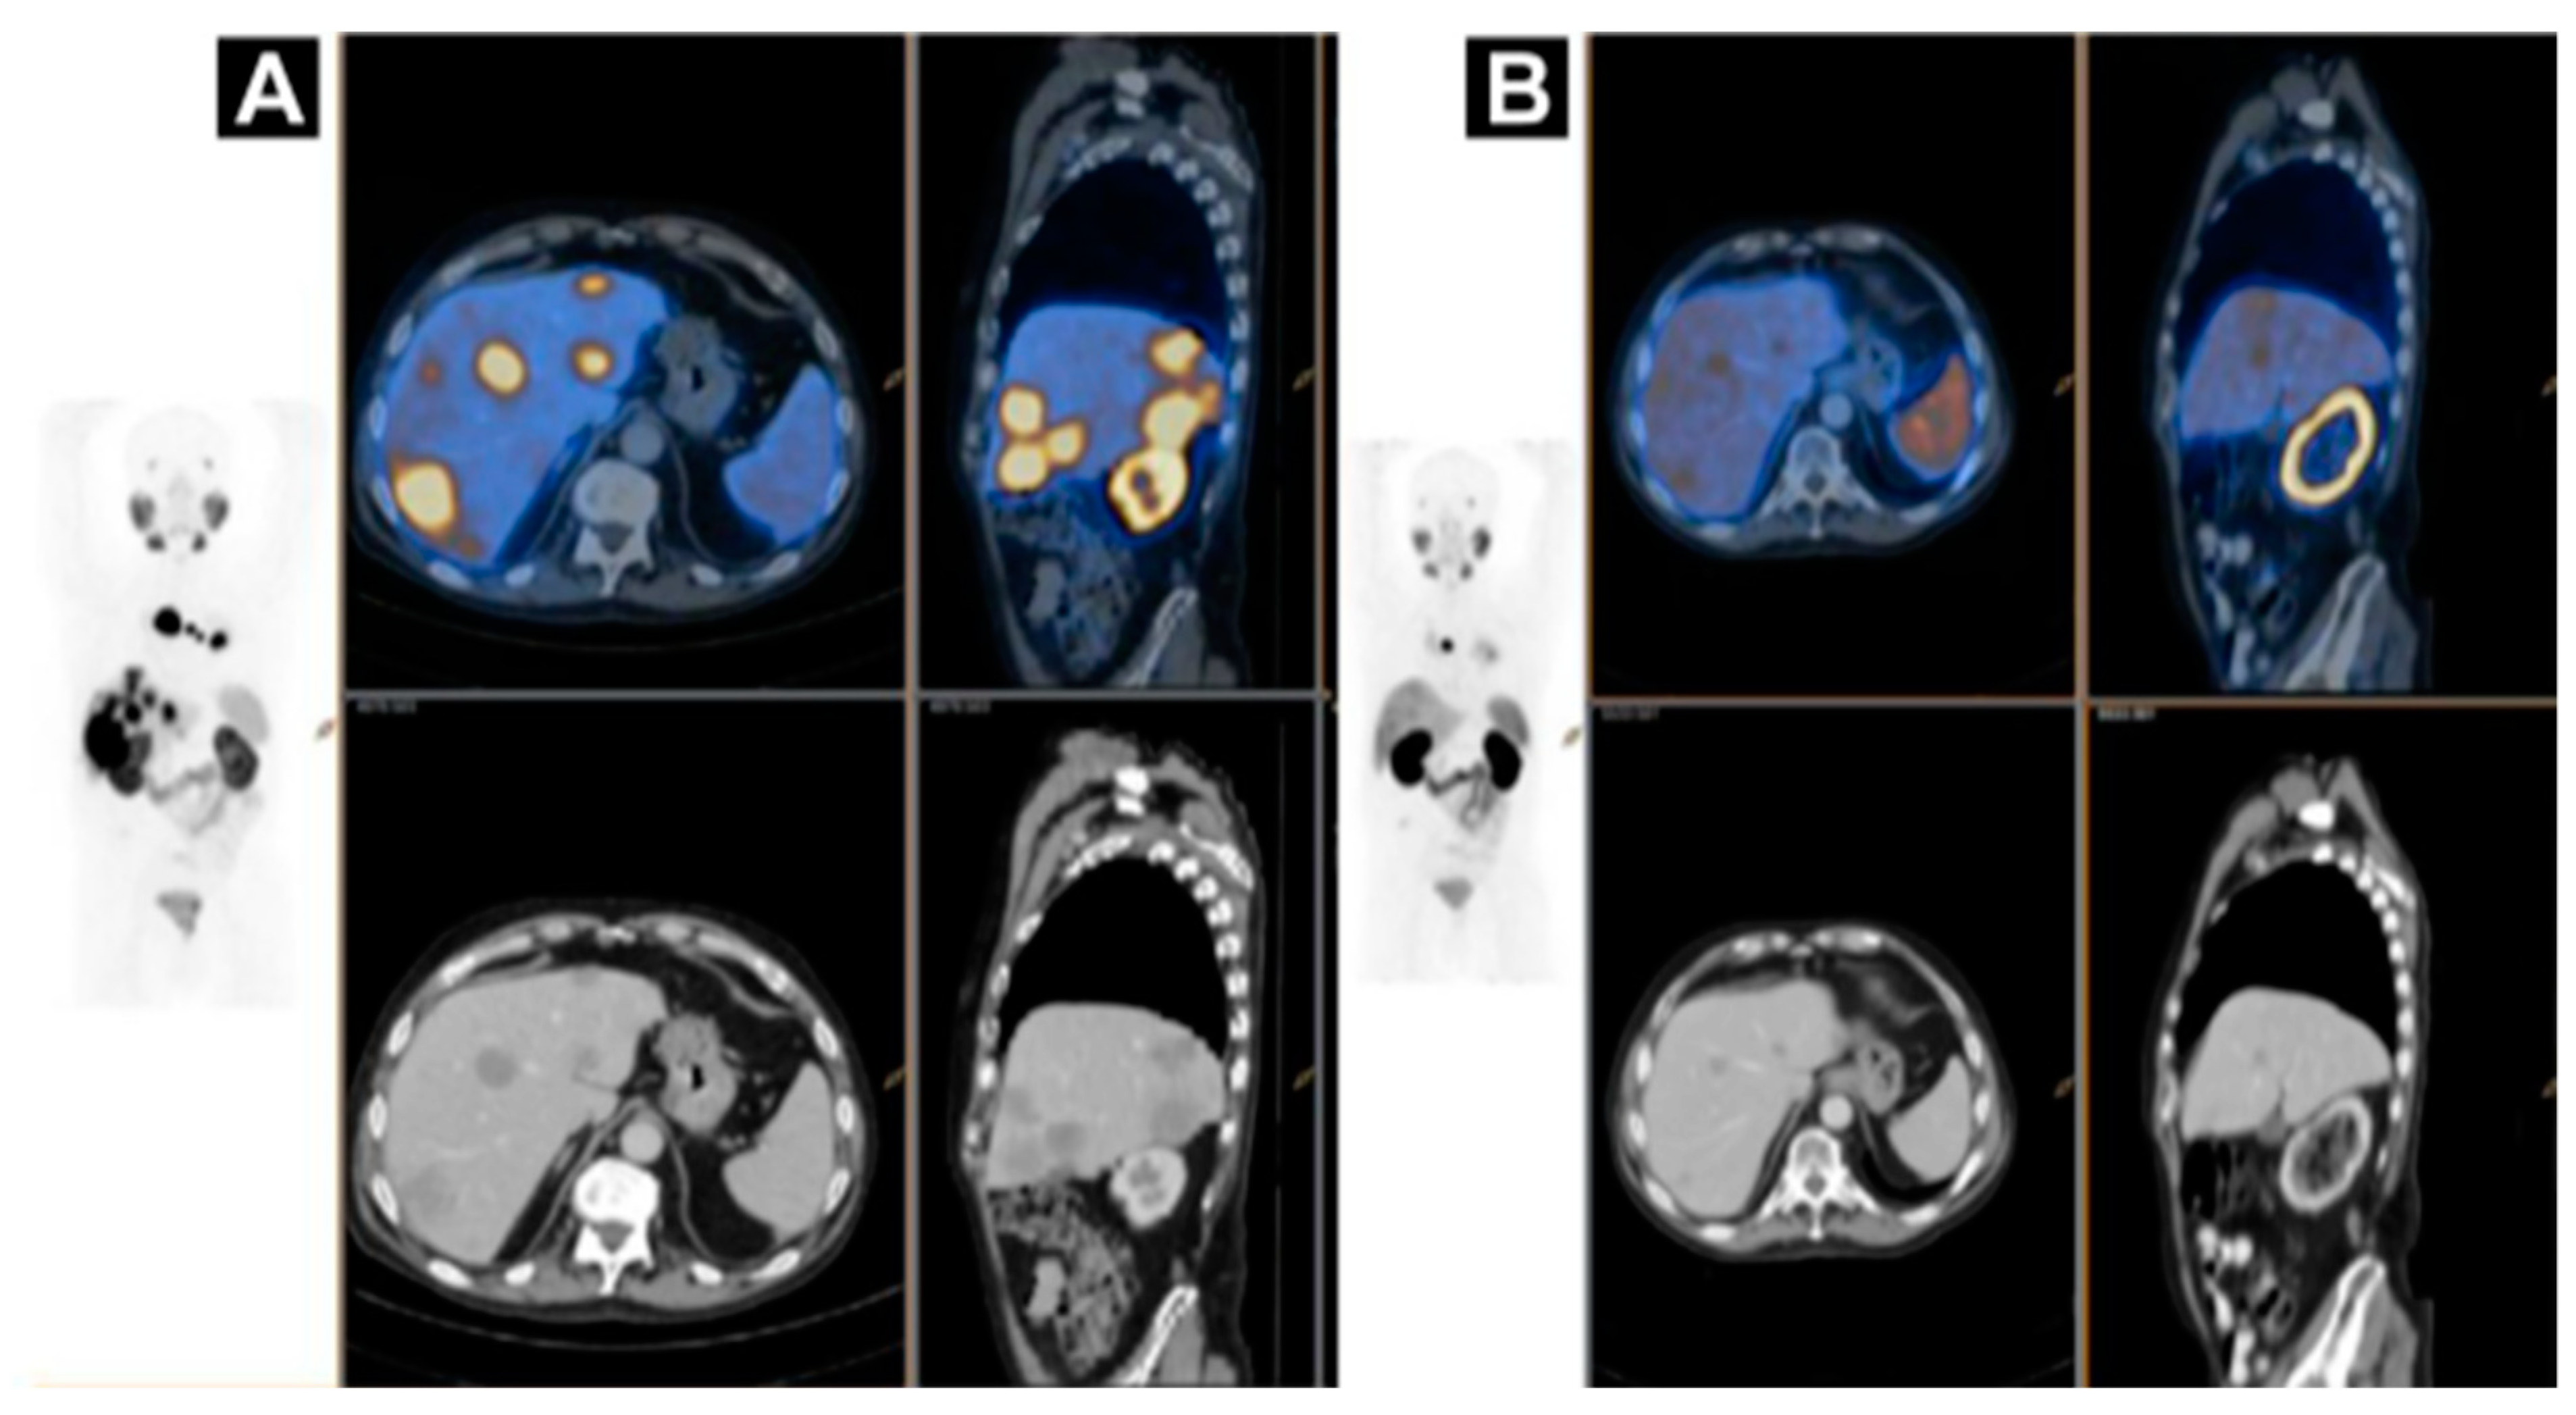

Figure 8.

A case of homogenous treatment response (A) [68Ga]Ga-HBEDD PSMA-11/PET-CT: Highly PSMA-avid liver and mediastinal lymph nodal metastases (SUVmax 70) on screening (PSA 340 ng/mL). (B) [68Ga]Ga-HBEDD PSMA-11/PET-CT: 3 months after 4 cycles of [177Lu]Lu-PSMA therapy (PSA 1.5 ng/mL) exhibited marked biomarker and RECIST response with minimal residual PSMA activity in liver metastases and solitary PSMA-avid mediastinal lymph node. Reproduced from [146].

Figure 9.

(A) Pre-therapeutic imaging using [68Ga]Ga-PSMA-11 PET/CT delivering highest resolution; (B) Co-emission of γ-rays by Lu-177 enables imaging during therapy with [177Lu]Lu-PSMA-617; (C) 99mTc-PSMA scintigraphy has minimally less noise than posttherapy scanning and can be used for imaging follow-up in out-patient setting. GM 5 geometric mean; MIP 5 maximum-intensity projections; p.i. 5 after injection. Reproduced from [132].